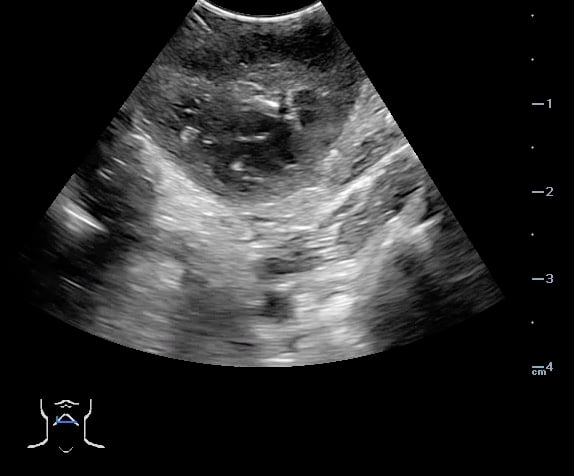

Peritonsillar abscess (PTA)33,34

- Significance of pathology:

- Complications of a PTA may include development of a parapharyngeal abscess, mediastinitis, airway obstruction, and other life-threatening pathology.

- Incidence of pathology:

- 37 per 100,000 PTA33,34

- Peritonsillar abscess is visualized as a hypoechoic or complex cystic structure

- Ultrasound-guided needle aspiration of a PTA:

- The depth of the abscess cavity from the mucosal surface should be noted to determine the length of the needle required to drain the abscess.